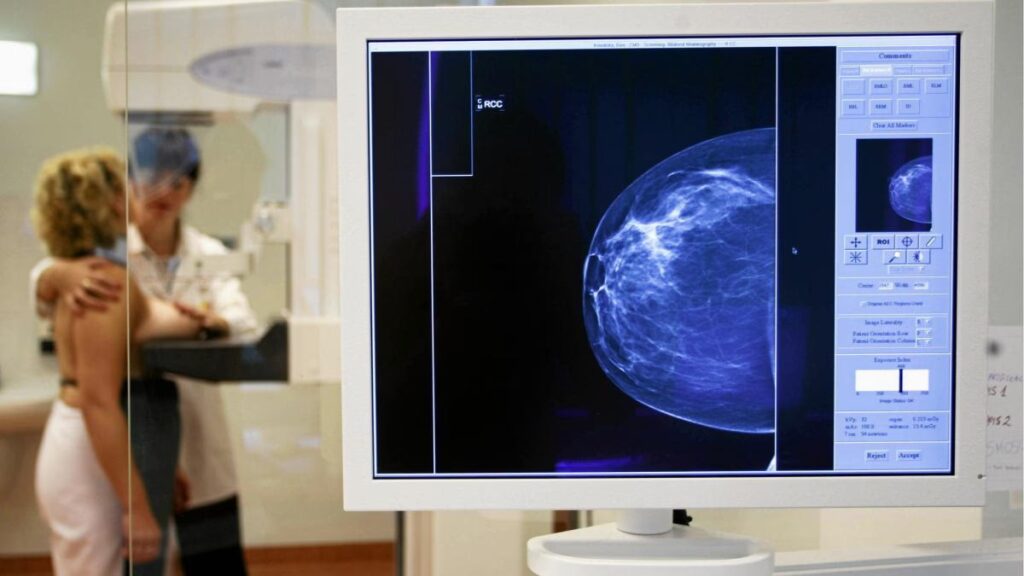

Mammografia to radiologiczne badanie piersi, wykorzystujące niską dawkę promieniowania rentgenowskiego. Jest to podstawowe narzędzie w diagnostyce raka piersi, pozwalające na wykrycie zmian na bardzo wczesnym etapie, często zanim staną się one wyczuwalne podczas samobadania lub badania lekarskiego. Mammografia umożliwia identyfikację mikrozwapnień, guzów oraz innych niepokojących zmian w strukturze tkanki piersiowej.

Badanie mammograficzne polega na umieszczeniu piersi między dwiema płytkami aparatu mammograficznego, które delikatnie ją uciskają. Ucisk ten, choć może być nieco niekomfortowy, jest niezbędny do uzyskania wyraźnego obrazu i zminimalizowania dawki promieniowania. Standardowo wykonuje się dwa zdjęcia każdej piersi.